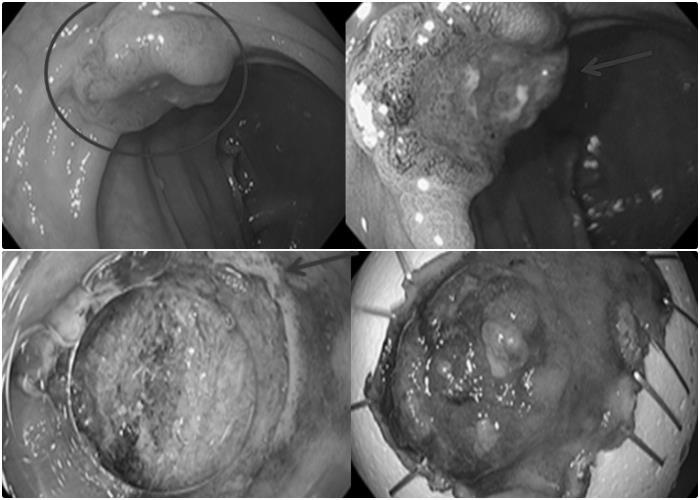

Kết quả nội soi, mặt sau hang vị dạ dày có một tổn thương nhỏ chỉ khoảng 0,8cm. Sinh thiết cho thấy có dấu hiệu viêm teo niêm mạc, dị sản ruột và loạn sản độ thấp. Trong khi đó, nội soi đại tràng lại phát hiện tới 4 polyp, kèm một tổn thương dạng lõm kích thước 1,2cm.

Sau khi cắt các polyp và tổn thương qua kỹ thuật ESD (nội soi cắt tách dưới niêm mạc), kết quả giải phẫu bệnh xác định ông mắc ung thư biểu mô tuyến đại tràng biệt hóa vừa, đã xâm nhập lớp hạ niêm mạc.

Hình ảnh tổn thương dạng lõm ở đại tràng.